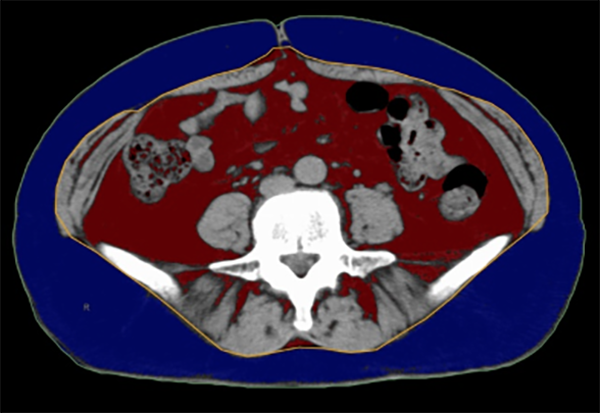

内臓脂肪測定では、X線CTを用いておへその辺りの内臓脂肪面積を測定します。

赤が内臓脂肪 青が皮下脂肪